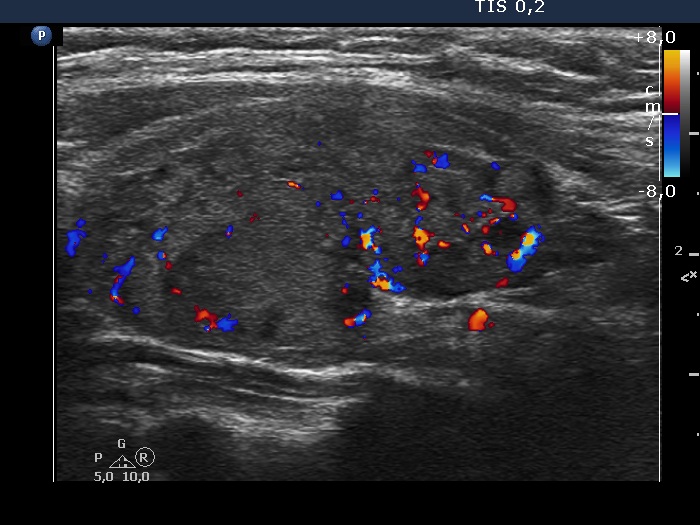

Left lobe, longitudinal view, color Doppler mode. The vascularization is average.